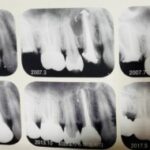

歯根吸収

歯根吸収 佐賀市 歯科 佐賀市の歯医者、当院こども歯科医院です。 根管治療の領域 ...